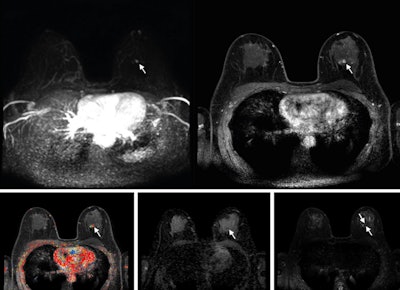

Abbreviated axial MRI images show a 7-mm irregular mass with irregular margin (arrows) in the right upper inner quadrant with early rapid enhancement (BIRADS 4). The participant was recalled and underwent an MRI-guided vacuum-assisted biopsy that showed sclerosing adenosis with microcalcifications and usual ductal hyperplasia and focal apocrine metaplasia. On the full-protocol images (not shown), the lesion was T2-weighted hypointense and showed diffusion restriction and washout kinetics in the delayed phase, characteristics that would not have reversed the decision to recall the participant.RSNA